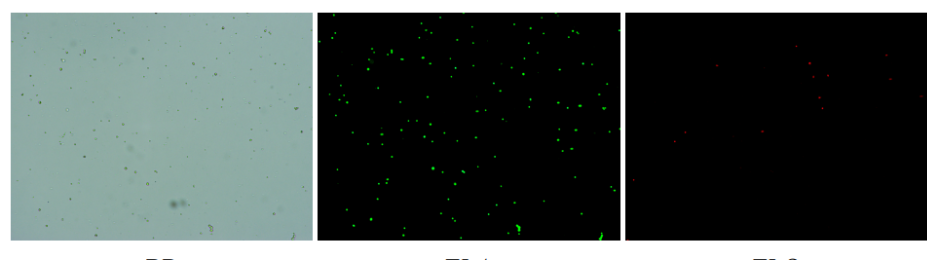

人膽管癌樣本,活性90.45%,結(jié)團率7.2%